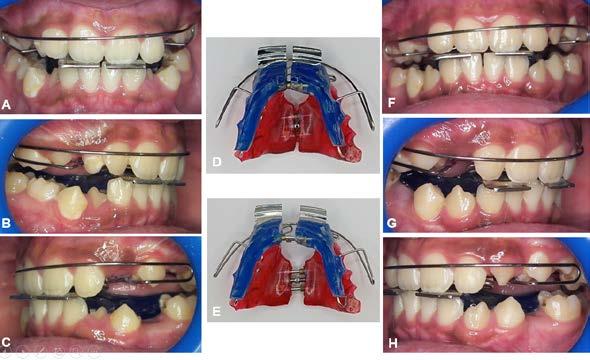

Figura 1. Fotografías intraorales y lateral de cráneo. A. Vista lateral (VL) derecha en oclusión. B. Vista frontal (VF) en oclusión. C. VL izquierda en oclusión. D. Radiografía lateral de cráneo.

Figura 3. Primer aparto SN1 con almohadillas vestibulares. A. VF con aparato, B. VL derecha C. VL izquierda. D. SN1, vista oclusal (VO). Después de 7 meses del tratamiento se observa los avances obtenidos por el aparato y los ajustes del mismo los cuales observamos en las figuras: E. VO del SN1 7mm de crecimiento transversal, F. VF con aparato, 3G. VL derecha, H. VL izquierda.

Investigación clínica

Figura 4. Segundo Aparato SN1. A. VF con aparato, B. VL derecha, C. VL izquierda, 3D. SN1, VO. Después de 5 meses del tratamiento se observa los avances obtenidos por el aparato y los ajustes del mismo los cuales observamos en la imagen, E. VO del SN1 5 mm de crecimiento transversal, F. VF con aparato, G. VL derecha, H. VL izquierda.

Figura 5. Tercer aparato PIPS A. VF con aparato, B. VL derecha, C. VL izquierda, D. PIPS VO. Después de 7 meses del tratamiento se observa los avances obtenidos por el aparato y los ajustes del mismo los cuales observamos en la imagen, E. VO del PIPS sin los mantenedores de espacio, 5. VF con aparato, 5G. VL derecha, 5H. VL izquierda.

radiculares de O.D. 73 y 83 y rehabilitación oral completa de O.D. 54, 63,65 y 75. Se procedió a colocar aparatos ortopédicos para corrección de la maloclusión en enero del 2022.

El tratamiento inicio con AOF, SN1 con Equiplan adicionando almohadillas vestibulares en el maxilar para despresurizar la acción de la musculatura labial. La indicación de uso fue utilizarlo de forma continua solo retirándose para comer e higienizar, activar del tornillo tanto superior como inferior una vez a la semana, y se realizaron revisiones mensuales en la clínica para valorar avances, llevar

a cabo activaciones, ajustes del aparato e indicaciones. Como se observa en la Figura 3.

Al haber obtenido los avances programados en la corrección de la sobremordida vertical con esté AOF, se decide cambiar a un nuevo SN1, con equiplan sin almohadillas y con arco vestibular esto para continuar regularizando el plano de oclusión en el paciente, y fue utilizado por 5 meses de forma continua. Se mantuvieron las mismas indicaciones de uso, que en el aparato anterior. Como podemos observar en la Figura 4

El AOF Sn1 logró el avance mandibular, expansión programada, armonización de arcadas y regularización de la curva de Spee, entonces se determina cambiar dicho aparato por unas PIPS, clase I para mantener el espacio que corresponde a los O.D. 35 y 45, ya que fueron indicadas para extracción los O.D. 75 y 85, esperando la erupción de premolares para terminar el anclaje. Las indicaciones para el paciente fueron uso continuo de las PIPS por 3 meses, solo retirándose para comer e higienizar, revisiones mensuales en la clínica para activación y desgastes de los mantenedores de espacio, vigilando la erupción de los premolares. Posteriormente se indicó su uso nocturno por 4 meses más para mantener estabilidad de los resultados obtenidos.

Figura 6. Fotos intraorales antes y después del tratamiento. A. VF B. VL derecha, C. VL izquierda, después de 18 meses de tratamiento D. VF, E. VL derecha, F. VL izquierda.